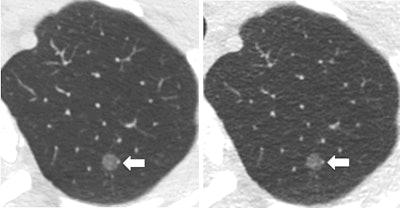

An ultralow-dose CT protocol involving computer-aided detection (CAD) matched the accuracy of standard CT for identifying lung nodules at just 10% of the radiation dose of a standard scan, according to an article published online July 25 in the Journal of Thoracic Imaging.

Researchers from the Mayo Clinic in Rochester, MN, tested a protocol that used lower tube energy and current with tin filtration and a model-based iterative reconstruction protocol (ADMIRE, Siemens Healthineers) to dramatically reduce radiation dose, down to a CT dose index volume (CTDIvol) of 0.4 mGy for a chest scan, compared with 5.3 mGy for a standard scan. To counter image noise and improve sensitivity, they applied CAD (syngo.CT CAD, VA 20, Siemens Healthineers) to the scans.

The ultralow-dose CT protocol had a comparable sensitivity to standard CT but required a much smaller radiation dose. The mean CTDIvol was 5.3 mGy for standard CT and 0.4 mGy for ultralow-dose CT, and the mean effective dose was 2.8 mSv for standard CT compared with 0.2 mSv for ultralow-dose CT -- a 92.6% reduction in radiation dose (p < 0.0001).